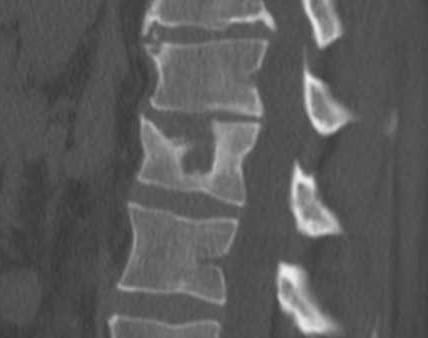

Suite à des sauts en parachute répétés je me retrouve avec un petit problème sur L1

je me fais faire un corset de Bohler pour 6/8 semaines, sympa pour travailler mais c'est toujours mieux qu'un fauteuil roulant; je vais cher l'orthoprothésiste, il me fait cela en CFAO deux rdv de 15 minutes, en partant je demande à payer(vieux réflexe)non monsieur tout est réglé par la secu.

Comme de bien entendu problème avec la sécu je demande le prix du corset.... 984,65 un truc en plastique, d'une précision de l'ordre du centimètre avec 4 sangles de sérrages qui doit durer max 2 mois